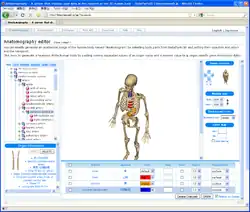

Anatomography is an interactive website which supports generating anatomical diagrams and animations of the human body. The Anatomography website is maintained by the DBCLS (Database Center for Life Science) non-profit research institute located at the University of Tokyo. Anatomical diagrams generated by Anatomography, and 3D polygon data used on the website (called BodyParts3D), are freely available under the Creative Commons Attribution-ShareAlike license.

Anatomography was launched on Feb. 9, 2009[1] by founder and chief director Kousaku Okubo, professor of the DNA Data Bank of Japan at the National Institute of Genetics.

Human body polygon data used in the site are called "BodyParts3D".[3] BodyParts3D polygon data are extracted from full-body MRI images. The MRI image set that BodyParts3D is based on is called "TARO". Taro is a common given name for males in Japanese, as John is in English. TARO is a 2mm * 2mm * 2mm voxel dataset of the human male created by the National Institute of Information and Communications Technology.[4] TARO was published freely in November, 2004.[5][6]

BodyParts3D polygon data are distributed in the OBJ file format. The entire data file's size is 127 MB (polygon reduced) and 521 MB (high quality) as of version 3.0.[8] The number of body parts (organs) registered in BodyParts3D is 1,523 as of version 3.0.[7]

BodyParts3D/Anatomography project uses the Foundational Model of Anatomy (FMA). The FMA is an open-source anatomical ontology developed and maintained by the Structural Informatics Group at the University of Washington. In BodyParts3D, each body-part is managed by an FMA identifier (FMAID) defined by the FMA. For example, the vertebral column is registered as FMA13478, the temporal lobe is registered as FMA61825, and so on.